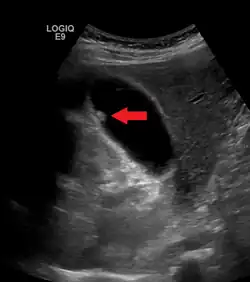

A polyp in the gall bladder as seen on ultrasound

Diagnosis is typically by ultrasound or CT imaging.